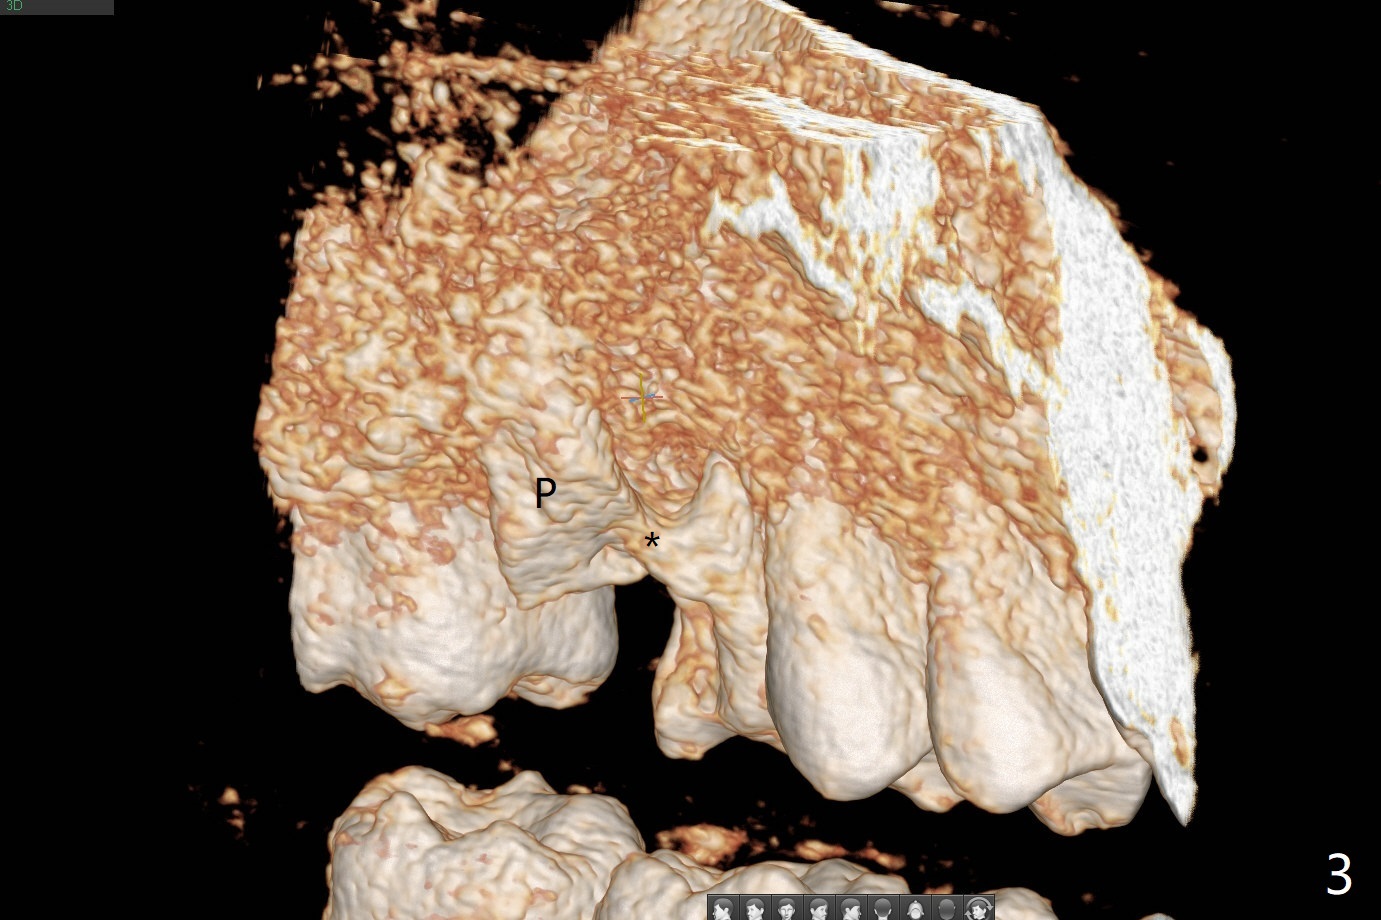

A 48-year-old man returns for implant at #14 after endo consult (Fig.1). The tooth appears to have fractured subgingival palatal (Fig.2,3 P). The furca is thin (Fig.3 *). A 5x10 mm implant will be placed slightly away palatal because of bone loss (Fig.4). Since the mesiobuccal (Fig.5 MB) and distobuccal (DB) sockets are close to the osteotomy (green), gauze with 1:50,000 Epinephrine (to reduce hemorrhage during sinus lift) will be placed away from the osteotomy (Fig.6 white area). In fact socket shield is conducted palatal.